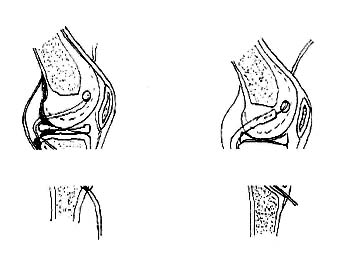

Todas las cirugías fueron realizadas por medio de asistencia artroscópica, para reconstruir el LCA. Se utilizó como injerto biológico el tercio medio del tendón rotuliano autólogo libre con el taco óseo de la tibia y de la rótula, de 1 cm. de ancho, 1 cm. de espesor y 2 cm. de largo, colocado dentro del ligamento sintético de poliéster (fig. 1.). Este ligamento, de acuerdo a las especificaciones del fabricante, tiene las siguientes características: fuerza de tensión hasta 276 kgf. y punto de estiramiento de ruptura establecido en 39%. El ligamento sintético junto con el tendón rotuliano fue colocado a través de los túneles femoral y tibial (fig. 2). El anclaje del componente sintético al hueso se realizó por medio de un tornillo de esponjosa canulado de 6,5 mm. más arandela al taco óseo en forma compresiva, debajo del cual se ataron tres hilos entrelazados de ethibone número 5 sujetados a los extremos óseos del tendón rotuliano. Se protegió la rodilla con una férula.

03_01_03_Fig1

Fig. 1 - El autoinjerto de tendón rotuliano dentro del ligamento sintético.

03_01_03_Fig2

Fig. 2 - Aspecto del ligamento stntettco